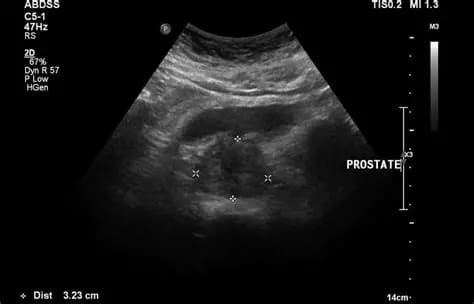

Endoanal Ultrasonography is a specialized imaging test used to evaluate the anal canal and surrounding structures using a high-resolution ultrasound probe inserted into the rectum. It helps detect fistulas, abscesses, sphincter damage, and other anorectal conditions.